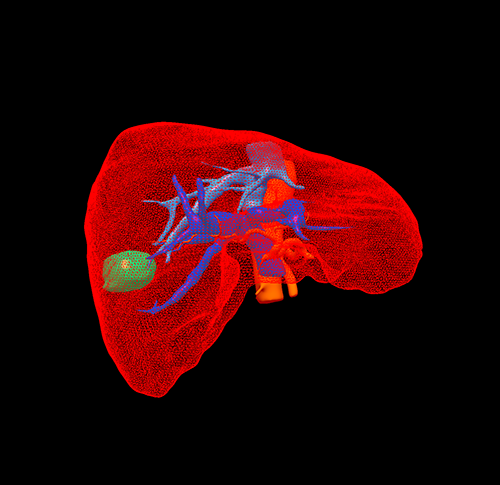

三维重建

S67肝癌--腹腔镜S67切除